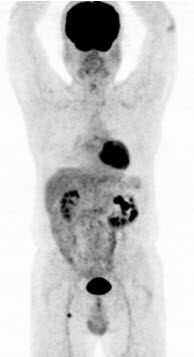

Hình 6. Bệnh nhân Vũ D.L., nam, 56 tuổi. Chẩn đoán: Non Hodgkin Lymphoma , GPB: WF7.Hình PET/CT trước và sau điều trị. Trước điều trị bệnh nhân có tổn thương hạch tại rất nhiều vị trí trong cơ thể: hạch cổ, hạch trung thất, hạch ổ bụng. Sau điều trị hóa chất 6 đợt, bệnh nhân được chụp PET/CT để đánh giá đáp ứng điều trị thấy các hạch hoàn toàn biến mất. Bệnh đáp ứng hoàn toàn.